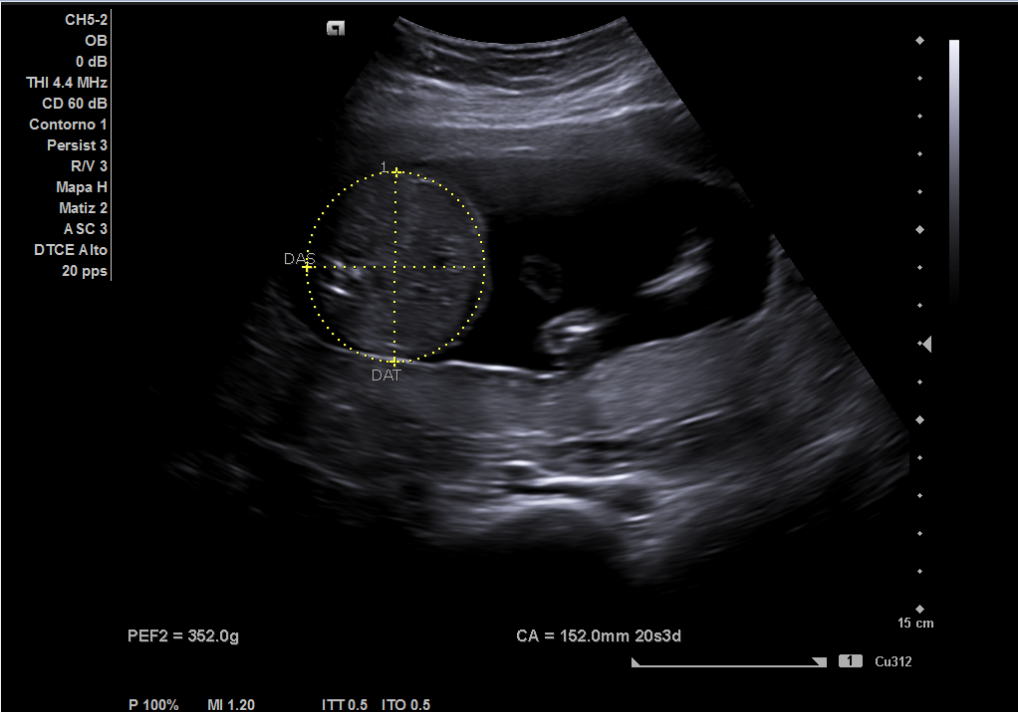

Ecografía: posición fetal con cabeza hacia la izquierda, bolsa más profunda de líquido amniótico de 7 centímetros, actividad cardíaca fetal normal (imagen 3), placenta ubicada en posición anterior, feto único. Se realiza medición de perímetro cefálico y diámetro biparietal (imagen 1) usando software de ecógrafo, así como del perímetro abdominal (imagen 2), estimando una edad gestacional entre 19 semanas y 1 día (cefálico) y 20 semanas y 3 días (abdominal).

Gestación normal. La ecografía realizada por Ginecología confirma una edad gestacional de 20 semanas y 1 día, realizada ese mismo día.